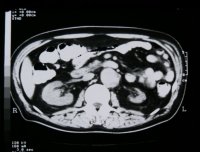

Computertomographie zur Diagnostik der kleinen Niere. Zum Beispiel eine pyelonephritisch veränderte linke Niere im Computertomogramm und im weiteren Beispiel CT und Organpräparat einer rechtsseitigen kleinen Niere.

Und in einem weiteren Beispiel CT und Organpräparat einer rechtseitigen "kleinen Niere" (Abbildung 11, 12ab).